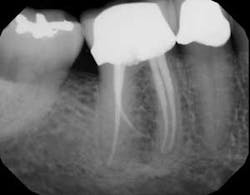

Each instrument and its accompanying technique have their own advantages and disadvantages. The key is to find a system to use in which all of the components are made to work together synergistically, such that they result in a procedure that is easy for the dentist to achieve the desired end results. In this instance, the desired end result is a debrided, clean canal that has been enlarged, shaped, and finished to receive a gutta-percha and sealed obturation (figures 1–4). This should be able to be achieved in an easy, quick, not too expensive, predictable, operator friendly manner. The dentist should not have to be Michelangelo to achieve the desired result consistently on every patient.